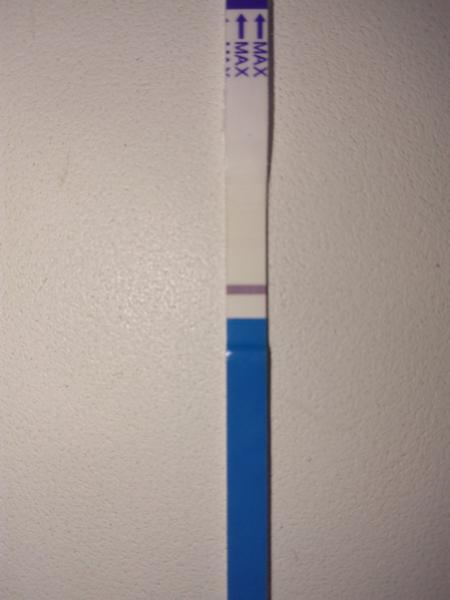

Vidím ducha,zkusila bych třeba až za 2 dny zda sílí(i když podle sebe vím že je těžké vydržet), já dělala každý den a čárka sílila každým dnem, tak držím pěsti

Takhle jsem to mela ja a vyslo to!